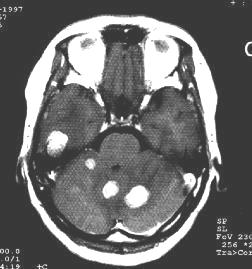

2.CT檢查 CT是目前診斷顱內轉移瘤的首選檢查手段,不僅在大多數情況下能發現腦轉移瘤,還能顯示轉移瘤的形狀大小、部位、數目、伴隨腦水腫及繼發腦積水和中線結構移位程度。CT顯示轉移瘤大多位於皮層或皮層下,圓形或類圓形,呈現低密度等密度、高密度或混雜密度。也可是囊性腫塊,囊腔內可有結節,伴有出血時可顯示出高密度區或液平面。若腫瘤生長快,可顯現出腫瘤中心部分的壞死及囊性變。周圍伴有明顯的低密度指狀水腫,鄰近側裂池或腦池受壓變小或消失,同側側腦室受壓變形、移位,移位明顯者可造成腦幹周圍池部分或全部消失此時患者病情常常很嚴重。強化後可顯示腫瘤呈環狀均勻或團塊狀強化,強化明顯者常提示腫瘤血供豐富,出血明顯者可掩蓋原有徵象易與腦出血混淆。環狀強化者可與腦膿腫混淆。位於顱後窩者常引起較明顯的梗阻性腦積水,四腦室受壓移位明顯,顱後窩特別是接近顱底病變由於偽影的影響常不易顯示,只能根據間接徵象推斷。丘腦及腦幹的轉移瘤常無明顯的腦水腫。水腫的程度與腫瘤惡性程度無明顯關係。CT骨窗位可清楚顯示顱骨受累情況。硬腦膜外轉移者,可見沿顱板下呈梭形或新月形高密度等密度病變。瀰漫型轉移者可見基底池、橋小腦角池等部位高密度影。

另外,不同病理類型的轉移瘤有其特有的CT表現。如肺腺癌和小細胞未分化癌轉移通常為高密度結節或環狀病變,有均一強化,水腫明顯。鱗癌通常為類圓形低密度腫塊,並有薄的環狀強化半數為單發。

3.MRI檢查 MRI檢查不僅能進一步提供轉移瘤的影像學固有特點還能發現多個病變而易於診斷。因為MRI比CT能發現更小的腫瘤,且多發性病灶為轉移瘤的特點。對於顱後窩及近顱底的病變由於去除了骨質的偽影而易於檢出。典型的轉移瘤表現為長T1、長T2信號,周邊有更長信號的水腫帶由於T2加權像上水腫常呈明顯長T2信號,因此比T1加權像更易於發現病變,特別是易於發現較小的病變。有些具特徵性的轉移瘤的T2加權像上可表現為等信號或略低信號。MRI可清楚顯示轉移瘤鄰近的腦回及重要結構受累情況有助於指導手術入路,瘤內有出血者可顯示出不同時期出血的特有MRI表現由於血-腦脊液屏障的破壞,轉移瘤可表現為明顯強化。對瀰漫型引起腦膜轉移者可清楚地看出腦膜的增厚而易於檢出。